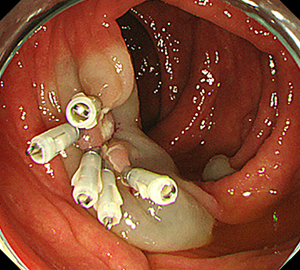

内視鏡的粘膜切除術(EMR)

外来にて切除することの出来ない、比較的大きめの大腸ポリープや平坦な病変などの切除の際に行います。

| 1:ポリープを見つけ、NBI併用拡大観察をした後、 | 2:ポリープ直下の粘膜下層に局注液を注入し盛り上げます。 | |

| 3:ポリープをスネアに通し、周囲の正常粘膜を入れて病変を絞扼 | 4:電気を流してして切除します。 | |

| 5:切除面をクリップで縫合閉鎖し、回収した検体の病理検査に提出します |